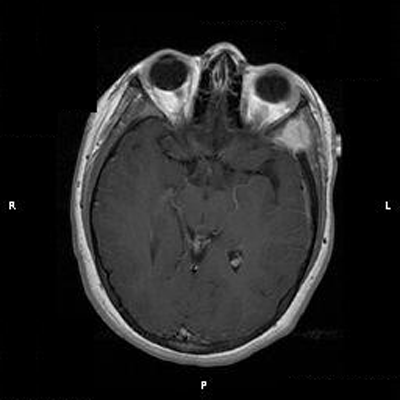

Clinical information: The patient was a 13 year-old girl who presented with worsening headache and some difficulties with memory, concentration and attention. MRI studies disclosed a 2.1 x 1.9 x 1.8 cm enhancing mass in the left temporal bone and sphenoid wing. The mass extended intracranially and abuts the left temporal bone accompanied by dural enhancement at that location. There is also extension through the bone into the submuscular temporal region. The following photos are taken from representative regions of the lesion. Panel 1 and 2 are CT scans at soft tissue and bone density respectively. Panel 3 and 4 are T1 weighed images without and with contrast respectively. Pandl 5 is proton density image. Panel A to D are cytologic (squash) prepartion for intra-operative consultation. Panel E and F are frozen sections for intraoperative consultation. Panel G to L are paraffin embedded sections.